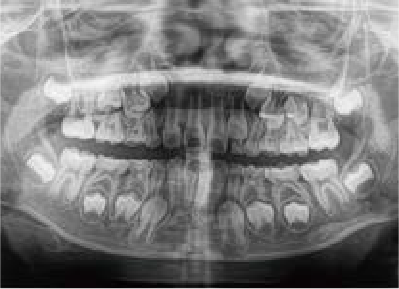

でこぼこ

でこぼこでも大丈夫。抜かずに、あごから育てる矯正治療

Jさん (矯正開始時:8歳)

Before

After

歯がガタガタに並んでいて、前歯の真ん中の位置が少し左にずれていました。

奥歯が生えるためのスペースが足りず、永久歯が生えて来られない状況が確認できました。

また、飲み込むとき下くちびるに力が入ってしまうクセが見られ、お顔全体の成長が遅れている様子が確認できました。

治療を終えて

歯がきれいに生えるためのスペースをしっかり確保することができ、歯並びを乱していたお口のクセも改善されたため、奥歯が生えるスペースを確保することができました。

しっかり噛めるかみ合わせを作ることが、将来の健康につながるので「よく噛む」練習も続けてもらっています。

主訴・治療内容 歯がガタガタになってきたことに悩み、無料相談に来院されました。

治療期間 3年

費用 462,000円(税込)